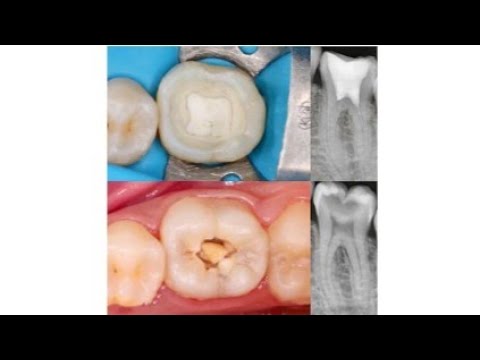

In this video, we dive into the essentials of Vital Pulp Therapy (VPT) — a minimally invasive alternative to root canal treatment aimed at keeping the dental pulp alive, even in challenging cases. You'll learn about:

✅ What VPT is (direct and indirect pulp capping, partial/full pulpotomy)

🧠 When it's appropriate — even for mature permanent teeth with deep caries or signs of irreversible pulpitis

🔍 Why it works — exploring the biological basis, including hydraulic calcium silicate–based materials like MTA and Biodentine